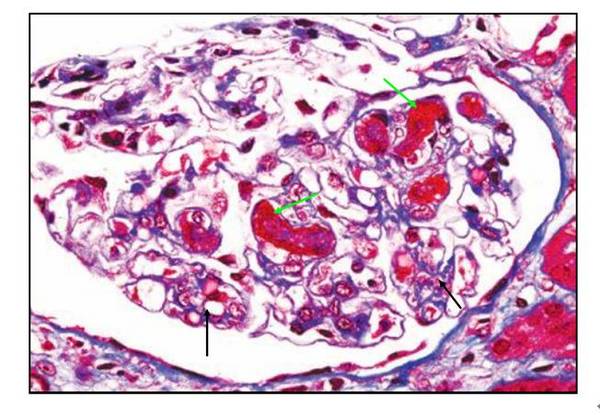

肾内病理图解:血栓性微血管病

4.微血栓,主要存在于前毛细血管,小动脉,小静脉内,只可见于显微镜下.